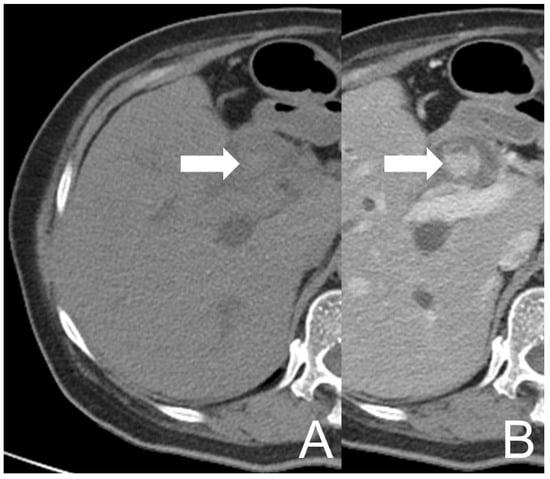

However, her symptoms recurred four months later. She visited our Emergency Department again where the abdominal CT showed an intramural lesion in CHD and CBD with mixed high and low densities and heterogeneous enhancement, accompanied with dilatation of the biliary tract (Figure 2). The picture was similar to that on the prior MRCP. She was treated as cholangitis and ERCP biopsy was redone for the neoplastic survey. During the procedure, CBD dilation with tissue retention and papillary mucosal surface were noted. Similar to the prior pathological report, descriptive diagnosis illustrating blood clots, histiocytes and some multinucleated giant cells aggregate was made. Antibiotics were used to treat the patient effectively.

Figure 2. UCOGC of CHD and CBD in a 66-year-old female, 4 months after the initial presentation. The axial CT images show a mass (arrow) in CBD, demonstrating relatively high density on the pre-contrast image (A) and heterogeneous enhancement on the post-contrast image (B). The imaging findings are compatible with a neogrowth with hemorrhage.